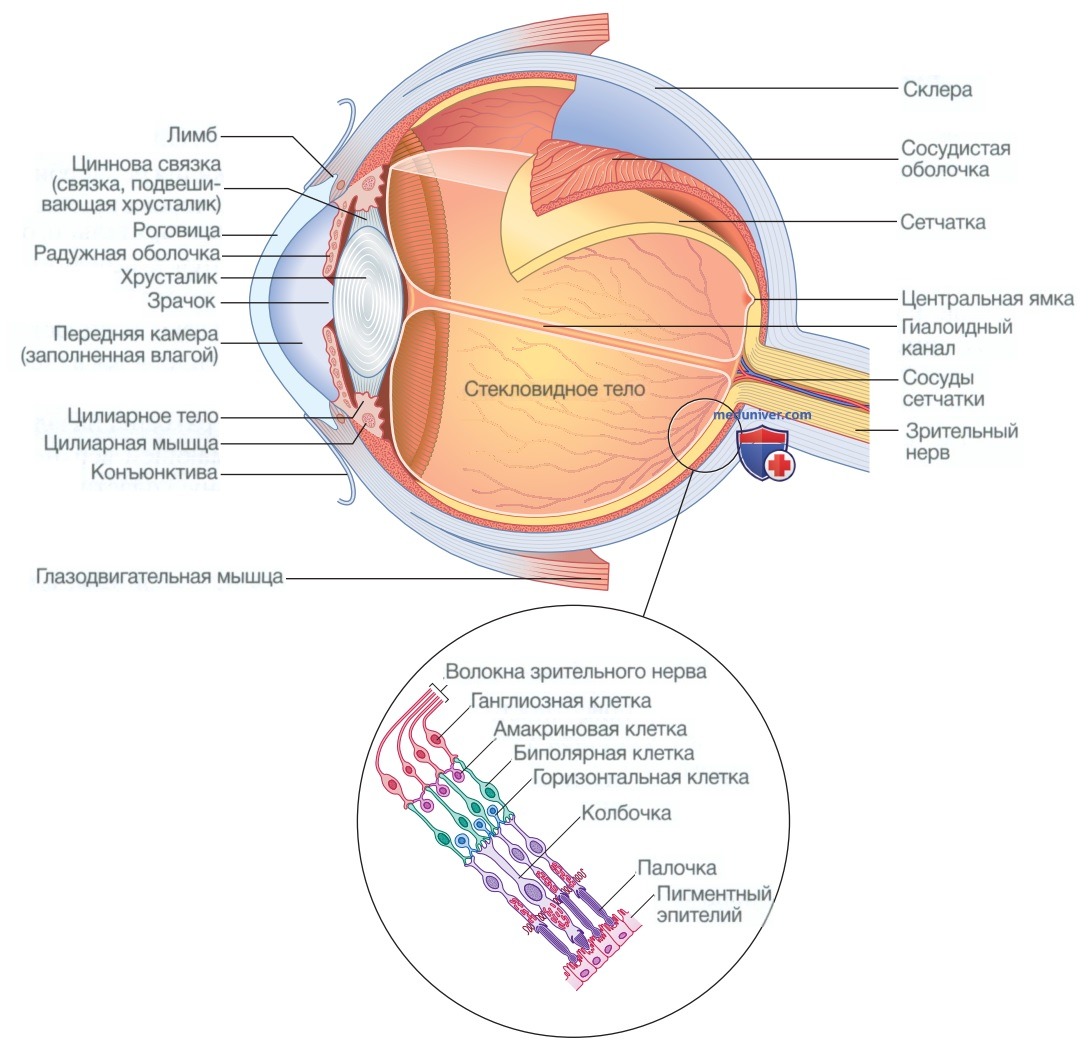

КТ-графики и изображение строения глаза